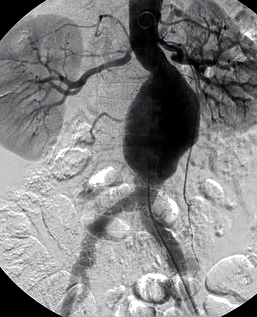

- ангіографія: дає змогу виявити деформацію аорти та її гілок, однак справжні розміри аневризми не завжди видно у зв'язку з можливою наявністю пристінкового тромбозу порожнини аневризми (рис. 2).

- комп'ютерна томографія (КТ) з контрастним посиленням: дає змогу точно виявити межі та форму аневризми й незмінених відділів аорти, обчислити розміри аорти та прилеглих артерій, оцінити ступінь їхньої звивистості. Одна з найбільш інформативних діагностичних методик, абсолютно необхідна для правильного підбору стент-графту.

аневризма аорти

Рисунок 5. Аневризма черевної аорти:

А - до втручання, Б - встановлено стент-графт